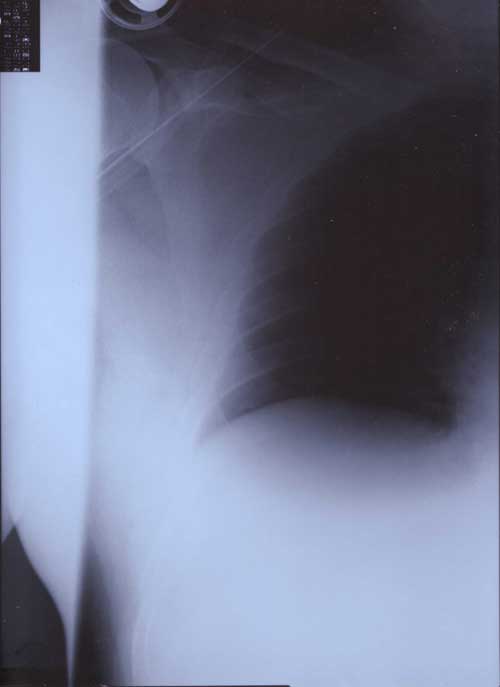

21st January 2000